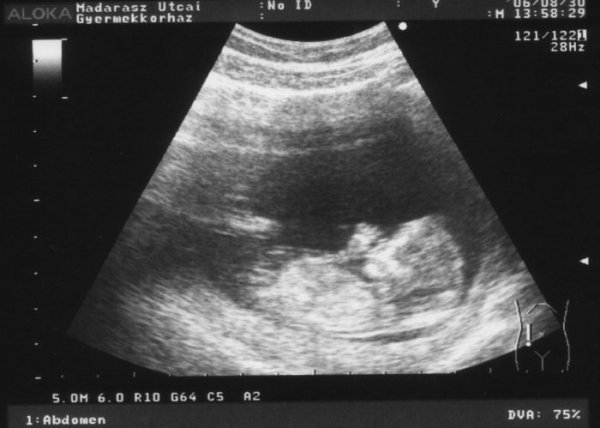

De a képeket még felrakom, mert én most "a boldogságtól ordítani tudnék..." Voltunk ma uh-n a férjemmel, és láttuk a babánkat mozogni is, cumizta az ujját, utánna két kézzel fogta a fejét(gondolom akkorra már eleg volt az uh-ból :oops: )

A képen jól látszik a bal keze, éppen cumizza :lol:

Ja, és már 6.5 cm!!! 2 hét alatt dupplájára nőtt!!! Pénteken megint uh, az már a hivatalos lesz, akkor néznek tarkóredőt!